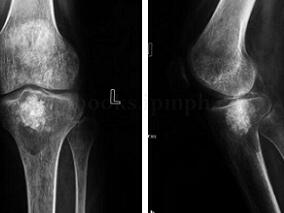

1小时条评论皮质旁骨肉瘤作为一种少见的骨的恶性肿瘤,有哪些特点?其预后与什么相关?骨肿瘤的诊断一定要遵循什么原则? (1)病例介绍 :患者,男,41岁,因右股骨远端肿瘤术后2年,右窝疼痛肿胀1年半入院。 2年半前无明显诱因出现右膝疼痛,夜间疼痛明显,口服止痛药可缓...